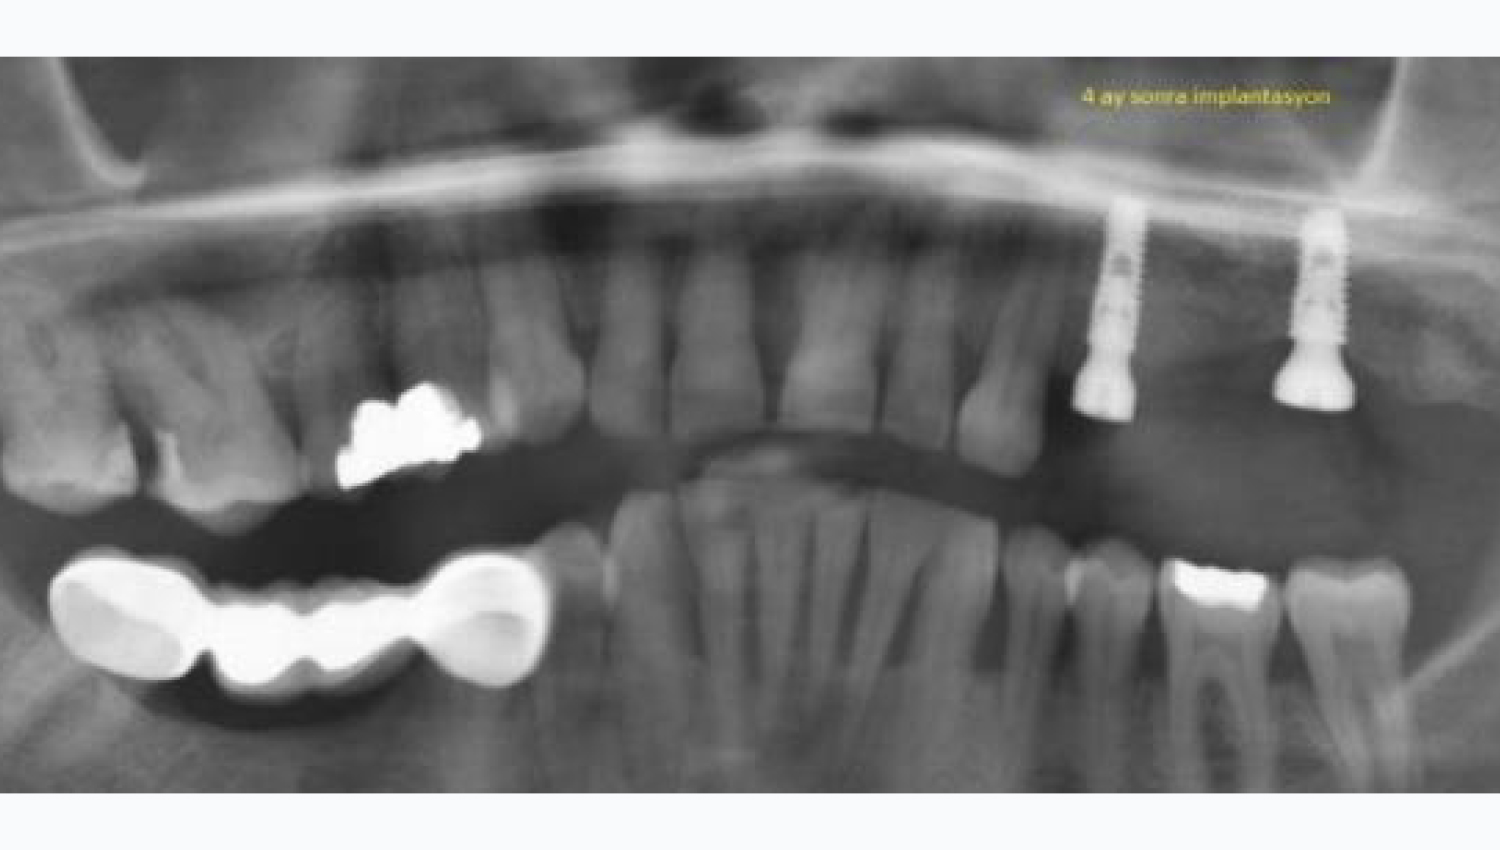

3. 4-month follow-up radiological imaging after implantation. The advantage of this technique is that in the internal sinus lift, it allows the sinus to be pushed more than 3 mm safely and allows a longer implant to be placed at the same time.